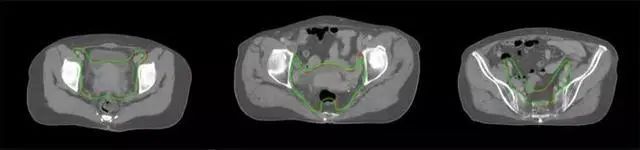

放射治療,簡稱放療,是治療腫瘤主要手段之一,利用放射線破壞照射區(qū)(靶區(qū))的細胞,使腫瘤細胞停止分裂直至死亡,醫(yī)生通常把放射治療形象的比喻為“打靶”,放療前精準勾畫腫瘤靶區(qū)范圍是腫瘤放射治療的關鍵步驟。傳統(tǒng)的靶區(qū)勾畫醫(yī)生會根據(jù)患者多張CT、MRI影像片憑借經(jīng)驗進行,比較耗時,治療的病人數(shù)量也有限,且靶區(qū)勾畫缺少行業(yè)統(tǒng)一的規(guī)范和標準,無法達到同質(zhì)化,勾畫精確度不理想。

技術(shù)原理

基于深度學習人工智能的放療靶區(qū)智能勾畫技術(shù)和自動計劃技術(shù),基于全面的市場調(diào)研和臨床專業(yè)意見,采用獨創(chuàng)的基于小樣本量的人工智能算法,實現(xiàn)放療靶區(qū)和危及器官的快速全自動勾畫。

產(chǎn)品優(yōu)勢

縮短至幾分鐘內(nèi)便可完成,大幅提升了放療效率,且人工智能平臺完成的靶區(qū)勾畫可基本滿足臨床醫(yī)生需求,專家只需審核時細微調(diào)整,可顯著提高靶區(qū)勾畫的規(guī)范化及精準度,讓放療智能化,標準化??筛采w食管癌、鼻咽癌、直腸癌、宮頸癌、肺癌等多種病種。